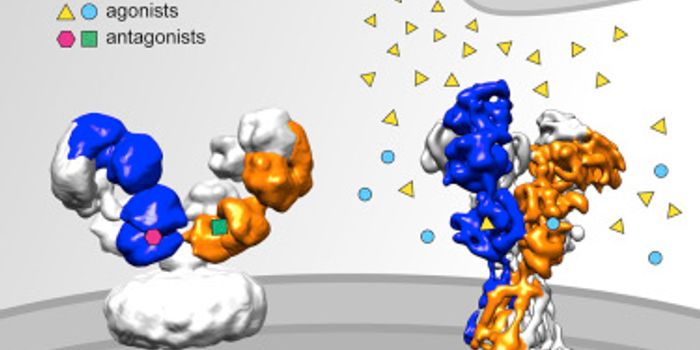

JUL 04, 2016NeuroscienceThe neuroscience behind medications for psychiatric conditions like depression, or anxiety is complex and often the subj ...